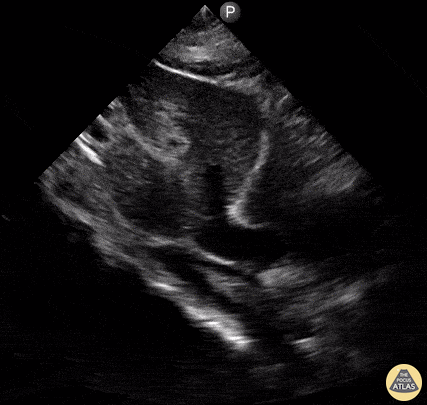

Seen here is a subxiphoid view taken from a patient admitted with symptoms of acutely decompensated heart failure. You can appreciate both a small pericardial effusion as well as a more noticeable pleural effusion. Reyna Huerta Sánchez, MD @DraHuerta09